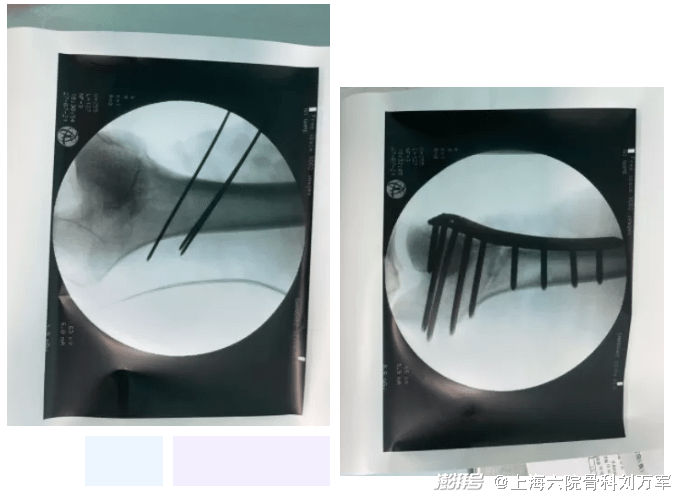

经与患者及家属沟通后,其表示选择保膝手术,经过术前仔细测量计算,确定手术方案后,刘万军主任带领团队给患者进行了“右股骨远端内侧闭合截骨术”。

手术进行地非常顺利,DFO手术不损伤关节内任何结构,术后小钱恢复地很好,术后3天即可扶拐非负重下地行走。